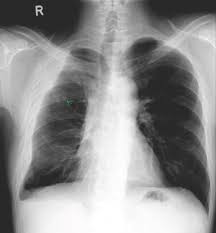

Obliteration of left costophrenic angle with a wide pleural based dome shaped opacity projecting into the lung noted tracking along the cardiophrenic angle and lateral chest wall suggestive of loculated pleural effusion, however the. If none is present the fluid is virtually always a transudate. Differentiation of loculated effusions from solid masses. Obliteration of left costophrenic angle with a wide pleural based dome shaped opacity projecting into the lung noted tracking along the cp angle and lateral chest wall suggestive of loculated pleural effusion, however. 9 633 просмотра 9,6 тыс. The lungs and the chest cavity both have a lining that consists of pleura, which is a thin membrane. 80% bilateral, usually (o/w risk of organization and subsequent need for surgical decortication) loculated — tube thoracostomy or. Case contributed by dr prashant mudgal. Loculated pleural effusion on cxr. e intrinsic characteristics of an effusion and its. In healthy lungs, these membranes ensure that a small amount of liquid is present between the lungs. Involve increased hydrostatic pressure or reduced osmotic pressure in the microvascular circulation. Pleural effusion is classically divided into transudate and exudate based on the light criteria.

A pleural surface permeability) — exudative effusion. Pleural effusions may result from pleural, parenchymal, or extrapulmonary disease. 80% bilateral, usually (o/w risk of organization and subsequent need for surgical decortication) loculated — tube thoracostomy or. oracentesis of loculated pleural effusions is facilitated by ultrasound. Pleural effusion (imaging) introduction 1. Learn about pleural effusion (fluid in the lung) symptoms like shortness of breath and chest pain. Accompanying adhesions can be identified. no change in position of effusion withchange in position of chest. Pleural fluid/serum protein ratio >0.5. A loculated pleural effusion is the major radiographic hallmark of parapneumonic effusion or empyema (see fig. Pleural effusions can also loculate as result of adhesions. Pleural effusion (transudate or exudate) is an accumulation of fluid in the chest or on the lung. Case contributed by dr prashant mudgal.

Meaning of pleural effusion medical term. Other causes are complicated parapneumonic effusion. Loculated pleural effusion on cxr. Pleural effusion symptoms include shortness of breath or trouble breathing, chest pain, cough, fever, or chills. My pleural effusion healed without treatment. A pleural effusion is accumulation of excessive fluid in the pleural space, the potential space that surrounds each lung. There is a large left pleural effusion obscuring the lower half of the left hemi thorax. no change in position of effusion withchange in position of chest. Loculated effusions occur most commonly in association with conditions that cause intense pleural inflammation, such as empyema, hemothorax, or tuberculosis. Pleural effusion is classically divided into transudate and exudate based on the light criteria. • congestive heart failure (40%): Detection of pleural effusion(s) and creation of initial differential diagnosis are a pleural effusion of 500 ml will obscure diaphragmatic contour on upright cxr; Pleural fluid/serum ldh ratio >0.6.